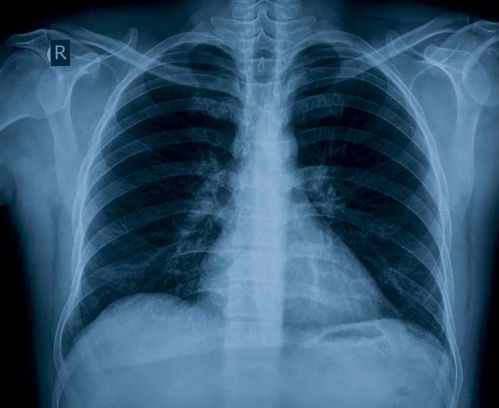

A: The main points to consider are the risk of pleural adhesions and pulmonary scar tissue caused by the thoracotomy, which can predispose you to pulmonary barotrauma.

Since barotrauma can occur with hyperinflation of lung tissue, a diver’s lungs must be able to tolerate rapid changes in volume and pressure. Fibrotic or scarred tissue is of concern to scuba divers because it has reduced elasticity and compliance in its interface with normal lung tissue. Any weakness in lung structure may be prone to rupture from even minimal over-inflation.

A high-resolution spiral lung CT scan may show the extent of scarring, adhesions and the presence of any air trapping. A follow-up appointment with a pulmonologist after the CT scan is necessary to exclude air trapping and adhesions before diving. The doctor will also consider any risk of recurrence of the condition that required the thoracotomy, any other medical conditions you might have, your overall level of fitness and your smoking history, all of which are necessary to consider before you return to diving. AD